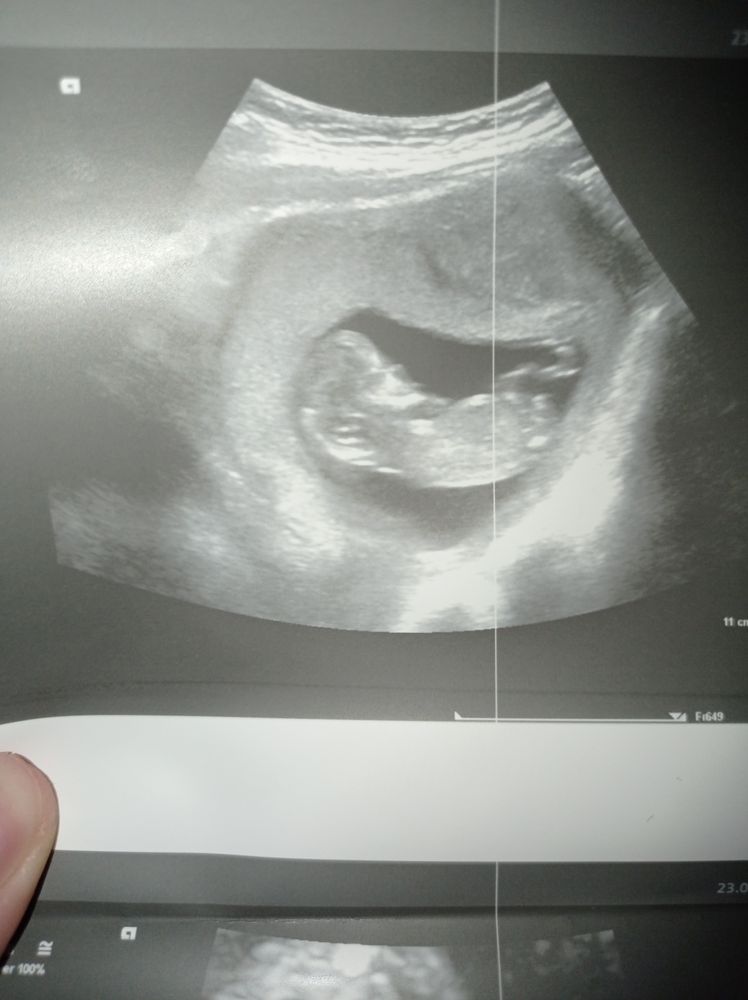

Пол ребёнка по узи, кто что видит?

Здравствуйте, видела тут девчонки на форуме, специалисты и видят по узи, нам уже 12 недель и 3 дня

Отписываю. На втором скрининге сказали мальчик, ждем третий